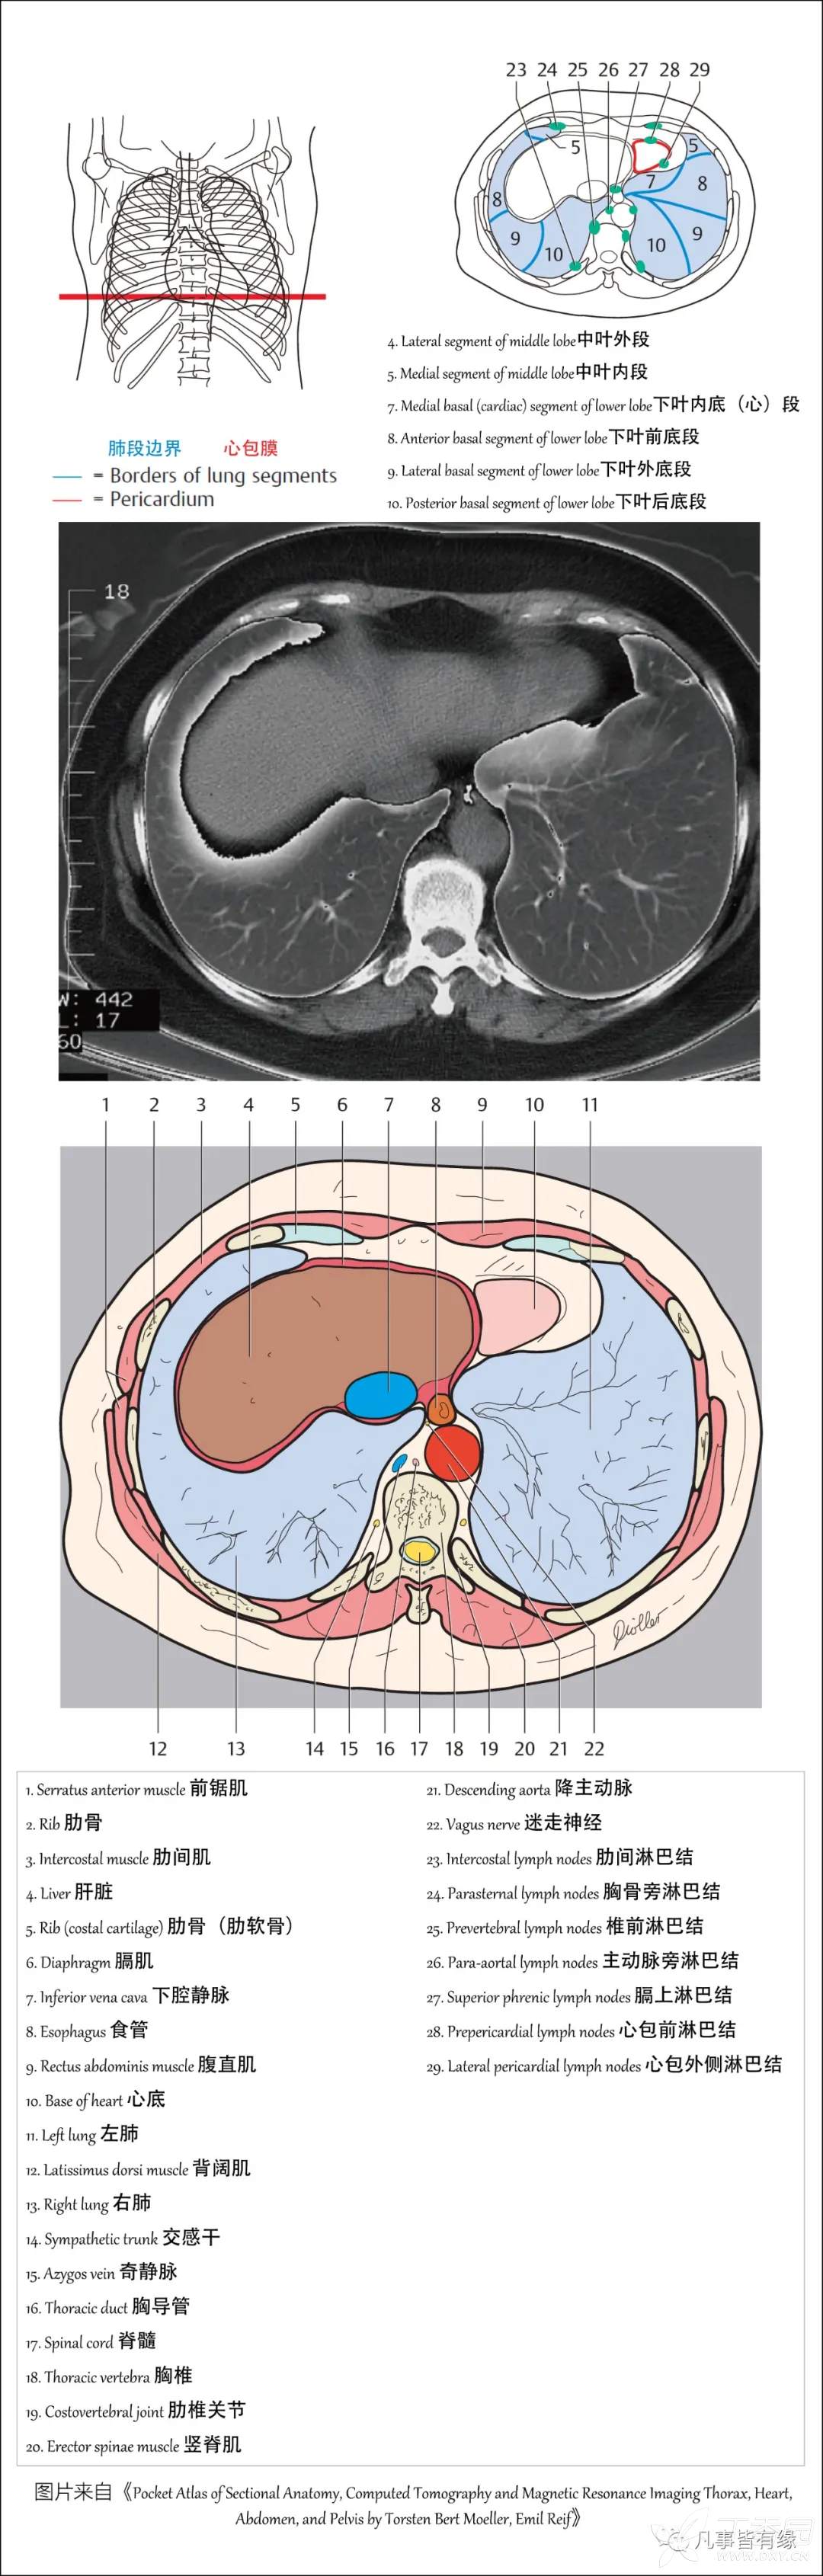

(一)胸部CT轴位断层解剖: